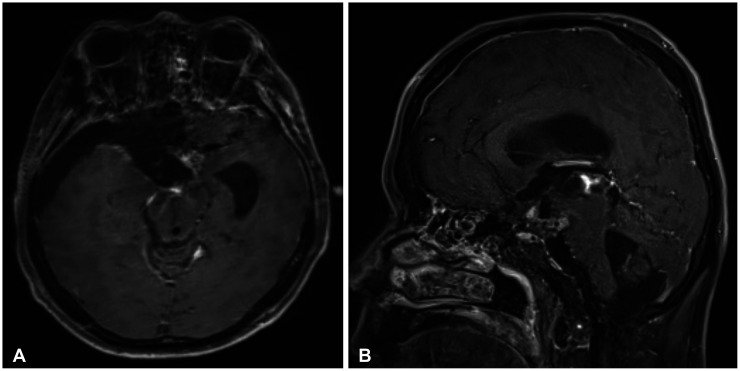

We report a rare and diagnostically challenging case of a 39-year-old male patient who presented with symptoms of dizziness and headaches, without any focal neurological symptoms. Initial imaging studies suggested a germ cell tumor, and an endoscopic biopsy led to a preliminary diagnosis of a pineal parenchymal tumor of intermediate differentiation. However, histological evaluation following surgical resection revealed the final diagnosis to be an ectopic pituitary neuroendocrine tumor (PitNET), a condition that is exceedingly rare. Ectopic PitNETs are uncommon tumors that develop outside the normal anatomical location of the pituitary gland. Their atypical presentation often leads to misdiagnosis as other intracranial neoplasms. This case highlights the diagnostic challenges posed by ectopic PitNETs and contributes to the limited literature on this rare condition. It underscores the importance of maintaining a broad differential diagnosis in patients presenting with atypical intracranial neoplasms.

Abstract Image